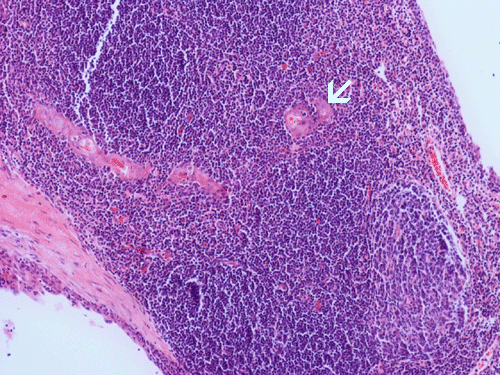

Histopathology: The lesion is encapulated cystic structure with the wall lined by nodules of lymphoid tissue (Panel A  and B) that are devoid of any evidence of hematopoiecic malignancy. Within this lymphoid tissue are small pink islands (Arrow in Panel C) and on higher magnification (Panel D) these islands are squamous cell nests. These islands are Hassell corpuscles and the lymphoid tissue is in fact thymic tissue. The cyst appears to have sustained repeated hemorrages. Both recent hemorrhage (Panel E) and cholesterol clefts consistent with resolved hemorrhage (Panel F) are present.